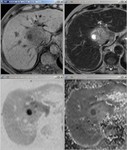

[画像診断]肝炎症性偽腫瘍(inflammatory pseudotumor:IPT)について 2010-07-13